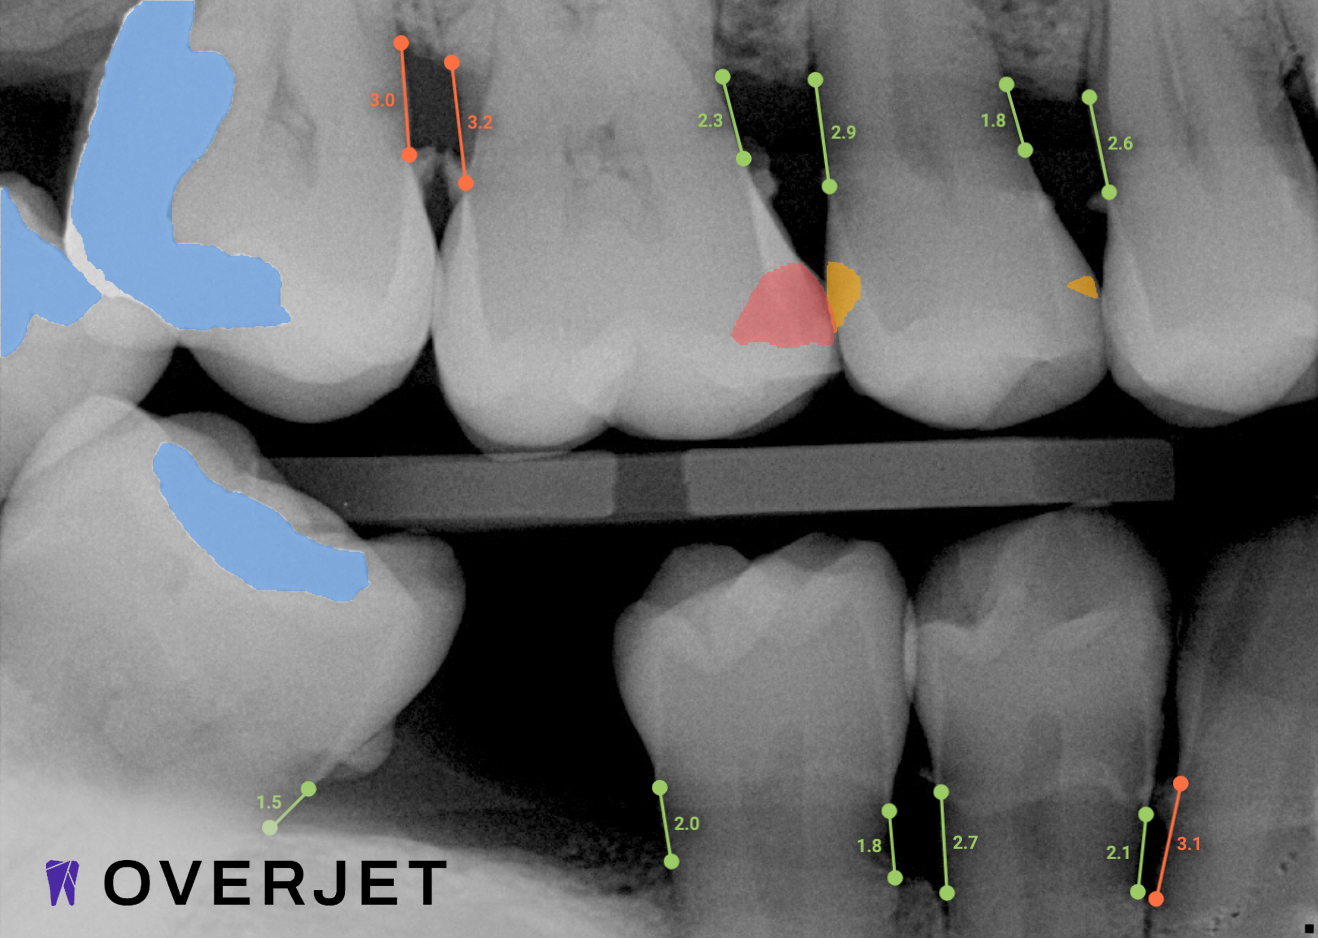

Overjet’s artificial intelligence technology transforms traditional black-and-white X-rays by adding a layer of data that instantly outlines decay (cavities) and measures bone loss. This makes it easy for you to see your results alongside your dentist.  It’s like getting a second opinion delivered instantly. With Overjet’s analysis and easy-to-read presentation, you will have the information you need to make an informed decision about your oral health. Together, we’ll review your findings and discuss the best steps to take to achieve your goals.